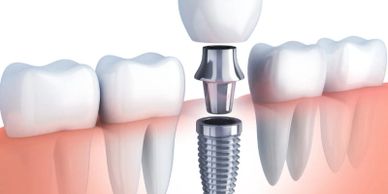

Dental implants are the best replacement for missing teeth. If properly cared for, they can last a lifetime. They can replace single teeth, multiple tooth spans, or even a complete set of upper or lower teeth.